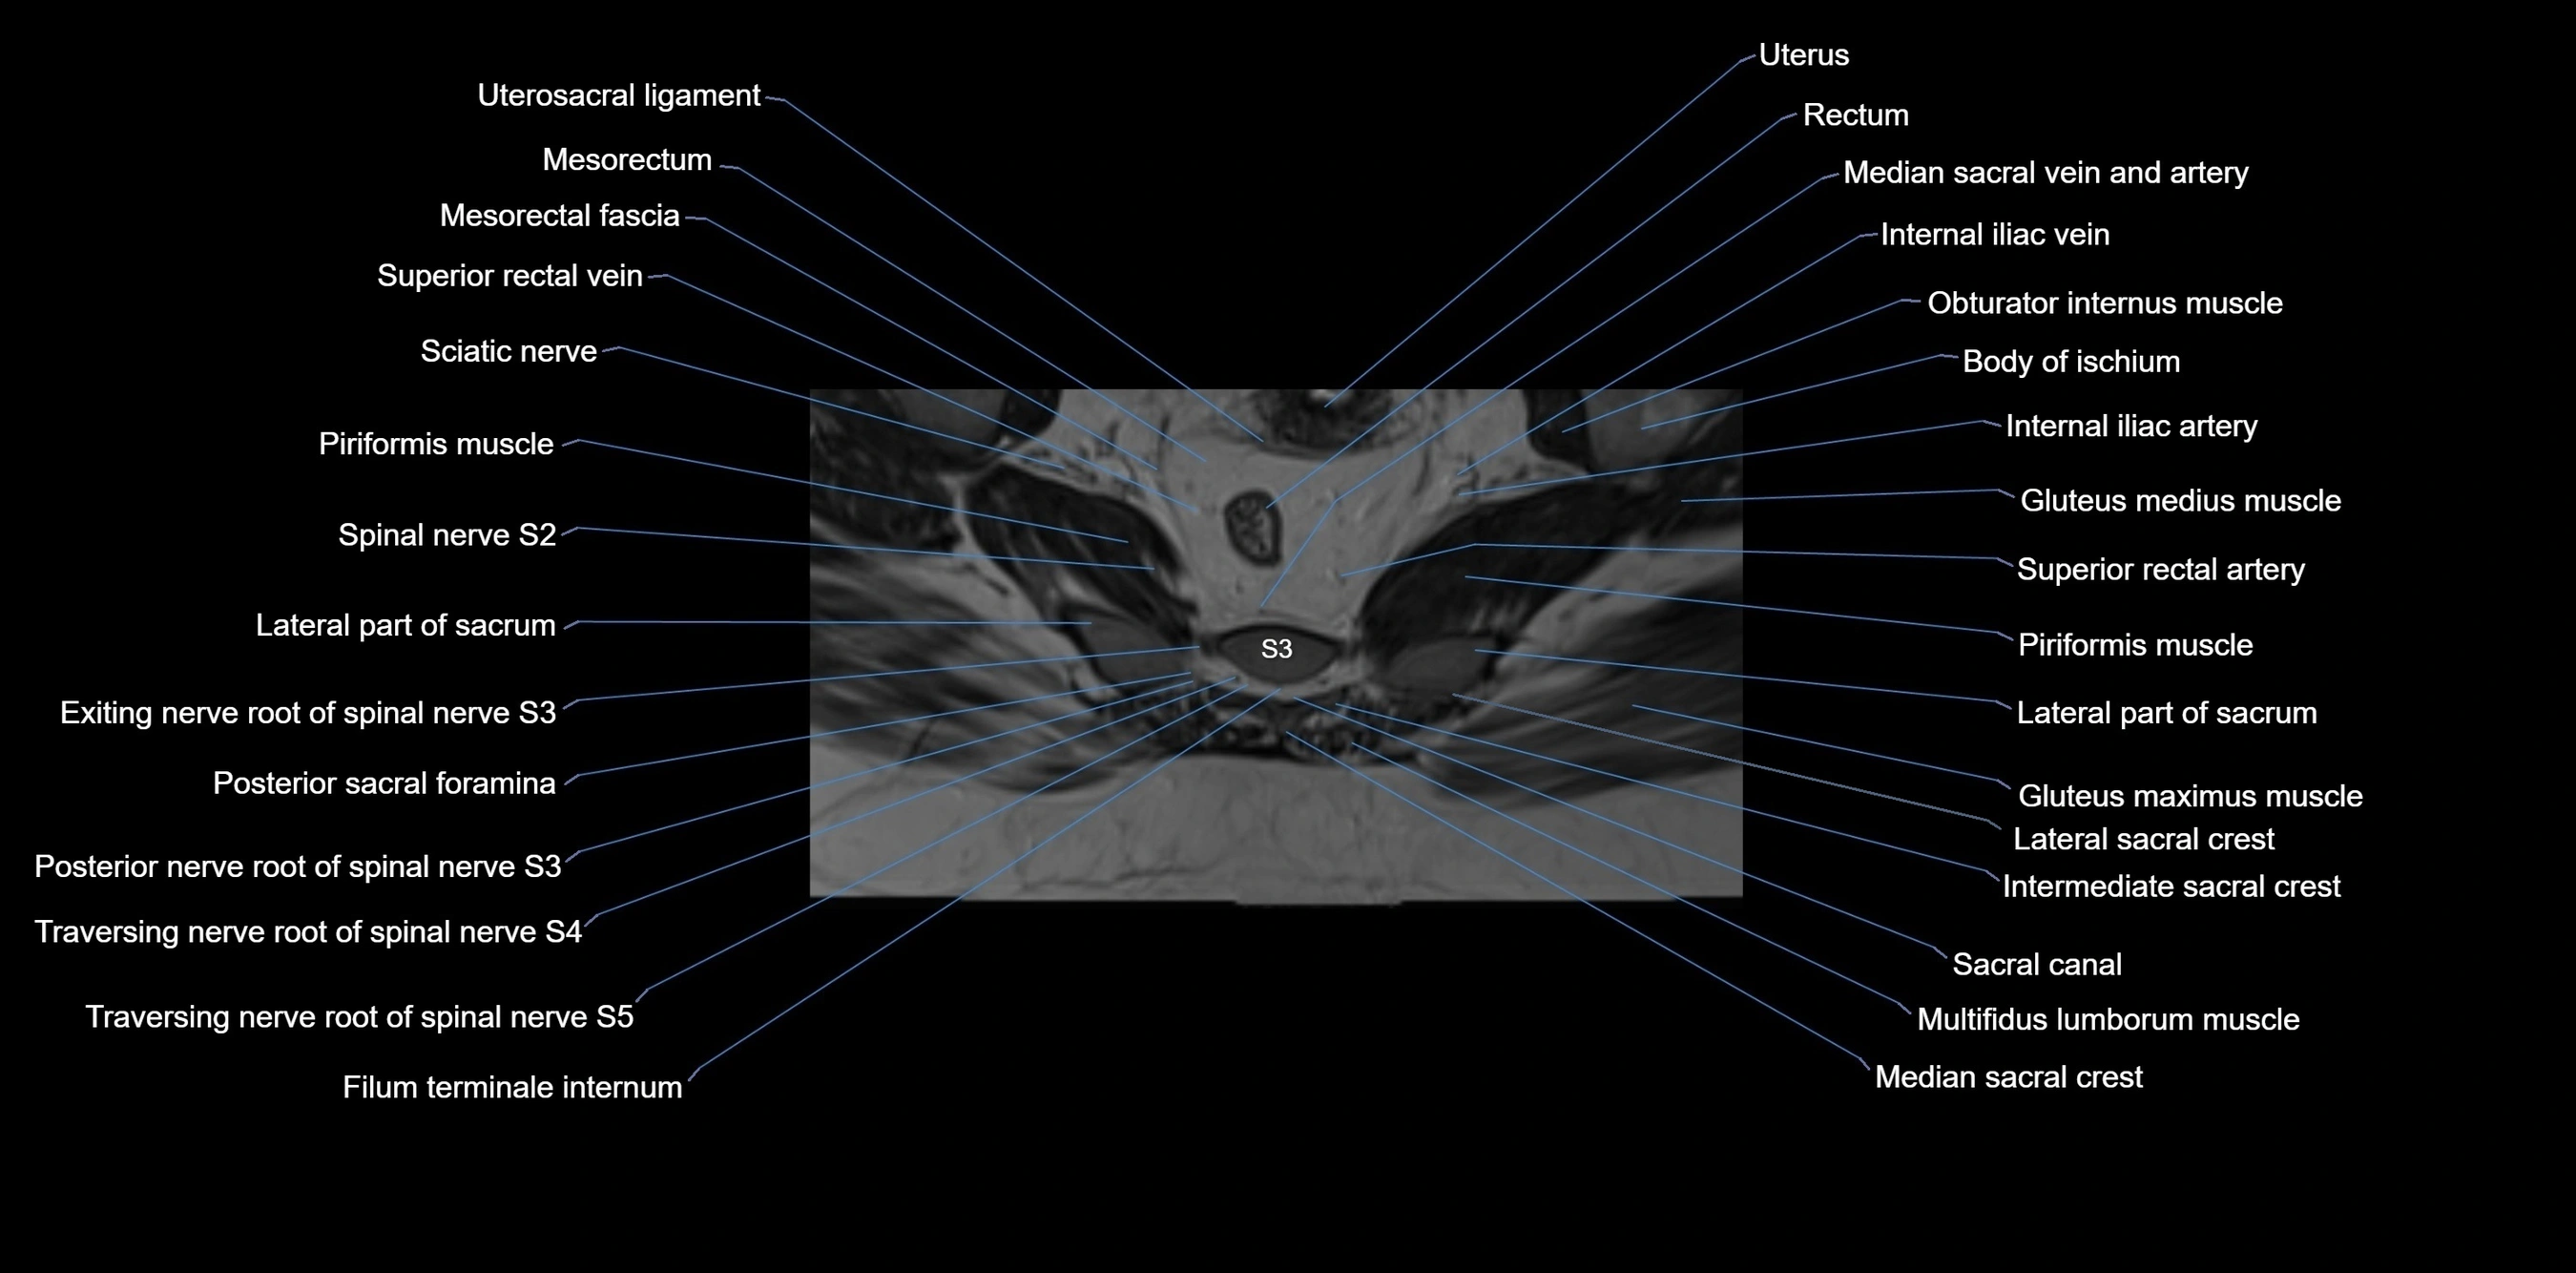

MRI image

image

MRI Appearance

T1-weighted images:

• Cortical bone appears very low signal (dark); marrow shows intermediate signal

• Iliac fossa fat is bright against low-signal cortex

T2-weighted images:

• Cortical bone remains dark

• Marrow signal varies depending on fat content; edema or tumor shows hyperintensity

STIR:

• Suppresses fat, making bone marrow edema, fractures, or infiltrative lesions appear bright

• Excellent for trauma, sacroiliitis, and metastatic evaluation